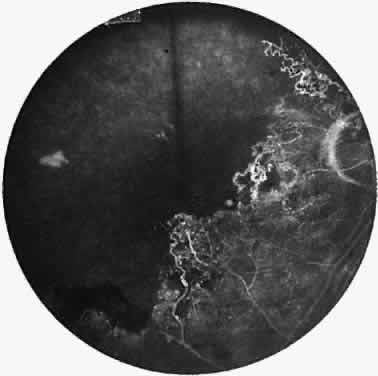

A varying degree of peripheral retinal nonperfusion is present in all patients with this disease. The nonperfusion generally is confluent and sharply demarcated from the posterior perfused retina (Fig. 3). Fine white lines representing the remains of obliterated large vessels (ghost vessels) often are seen in the area of nonperfusion. The temporal retina is most commonly affected.

Fig. 3. Fluorescein angiogram of the peripheral retina demonstrates the junction of normally perfused retinal vessels adjacent to an area of nonperfused retina. Notice the vascular abnormalities at the junction.

Elliot and Spitnas and colleagues have documented the abnormalities at the junction between the anteroperipheral nonperfused and the posterior perfused retina.9,10 Intraretinal hemorrhages often first appear in the affected area, followed by an increase in vascular tortuosity with frequent collateral formation around occluded vessels (see Fig. 3). Microaneurysms, arteriovenous shunts, and venous beading are commonly seen at the junction (Fig. 4). Fluorescein angiography enhances these abnormalities and often demonstrates staining at the stumps of obliterated vessels.

Fig. 4. Fluorescein angiogram demonstrating severe nonperfusion involving the macula. In this case, the macular nonperfusion was responsible for loss of central vision.